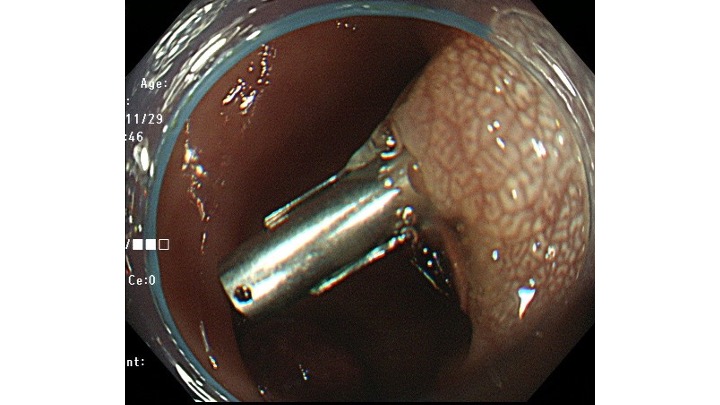

意外と基部は狭く、切除面積は少なくすみました。

後出血予防にCLIPをしています。